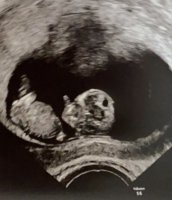

Var på TUL. Anbefaler volvat på Hamar. Gode bilder. 10+6.ca 4 cm lang. Litt mindre kvalm generelt, håper det fortsetter slik. ingen tydelig mage ennå, bare gass, men sliten. Symptomer kommer og går litt. Første barn. Valgte å ta TUL fordi jeg ville sjekke at alt stod bra til. Baby var sprell levende inni magen